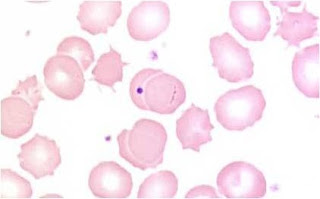

- a: Glóbulos rojos o eritrocitos

- b: Glóbulo blanco: Neutrófilo

- c: Glóbulo blanco: Eosinófilo

- d: Glóbulo blanco: Linfocito